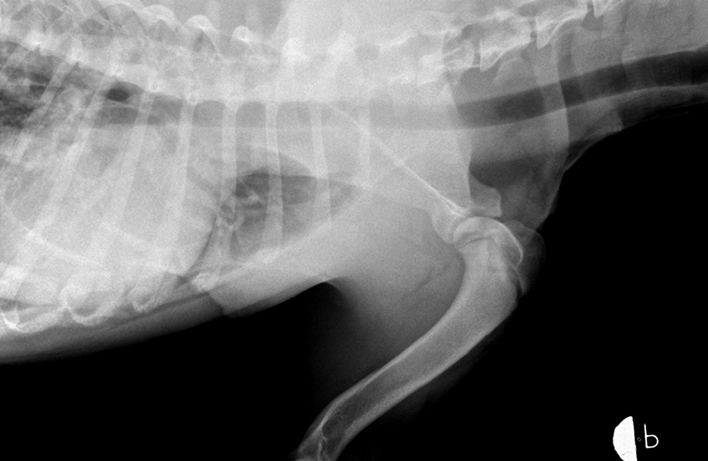

RTG Dysplazie kyčelního kloubu (DKK)